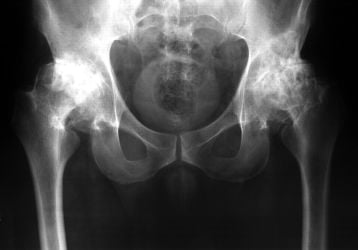

Двухсторонний коксартроз 1-2 степени: диагностика и лечение

В чем особенность двухстороннего коксартроза тазобедренного сустава 1-2 степени. Какие способы лечения существуют, методы профилактики и питание.